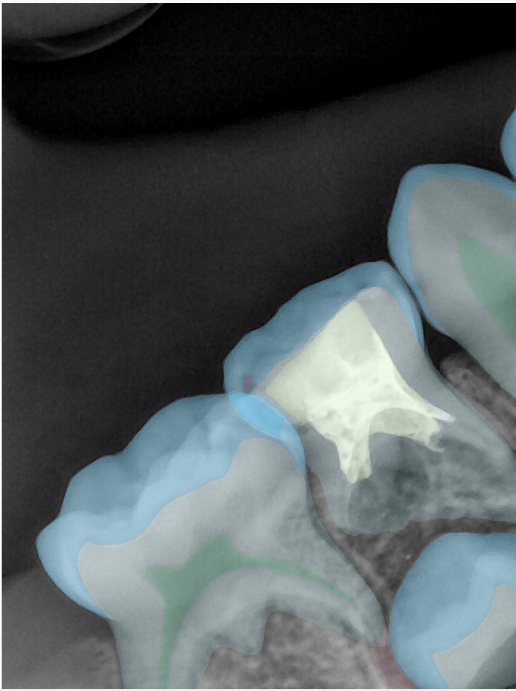

CR/DR 牙齿分割阶段记录

当前进展

- 完成了 CR/DR 牙齿相关分割训练

- 当前结果已经达到阶段预期,但仍有细节问题需要继续处理

相关测试

遇到的问题

- 训练过程中出现过 mask 下移问题

- 部分结果会出现 box 填充异常

- mask 边缘仍然有比较明显的锯齿感

参考

第二版算法问题测试